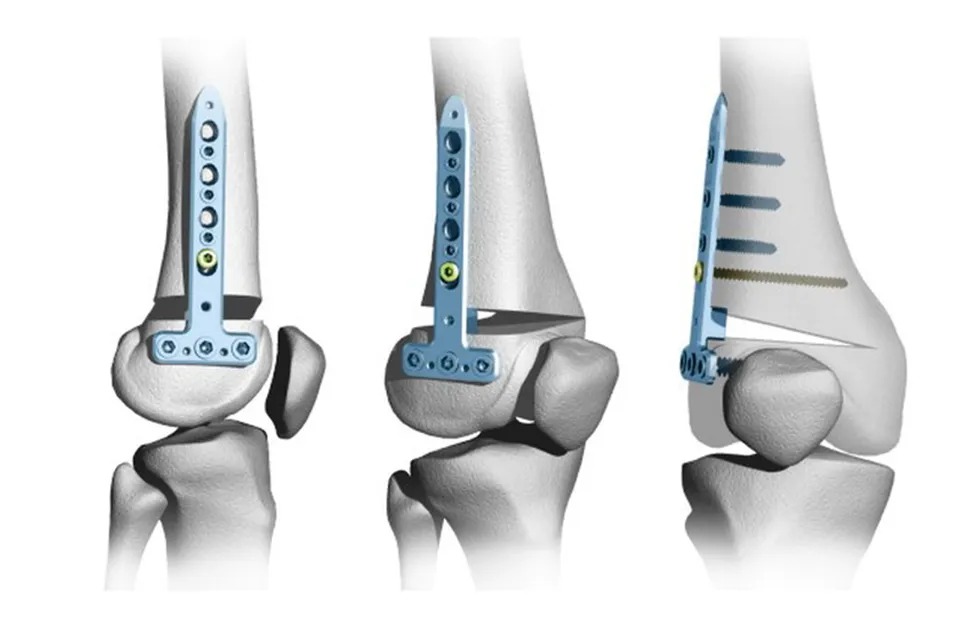

Корригирующая остеотомия как способ сохранить сустав и отсрочить протезирование

Боль в суставе и деформация оси конечности мешают жить полноценной жизнью, но замена сустава кажется преждевременной. Эта статья подробно объясняет, как корригирующая остеотомия исправляет биомеханику, снимает боль и возвращает подвижность.